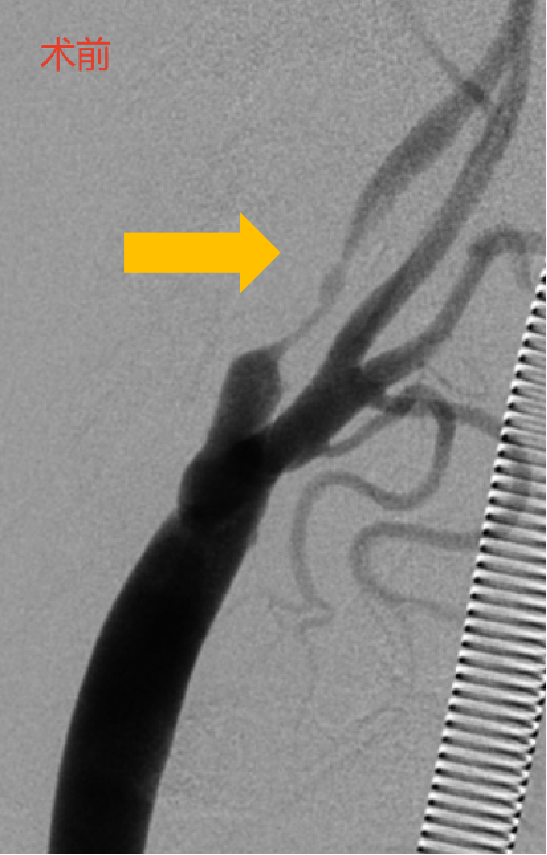

PT-CAS为颈动脉狭窄提供了更为科学、合理的腔内治疗方案,尤其是对于高位病变、不稳定斑块、严重狭窄甚至闭塞、入路条件苛刻的病例。

PT-CAS目前已成功完成了部分临床应用,取得了满意的近中期安全性和有效性,期待进一步的多中心临床研究,为患者早日带来更优的治疗方案。